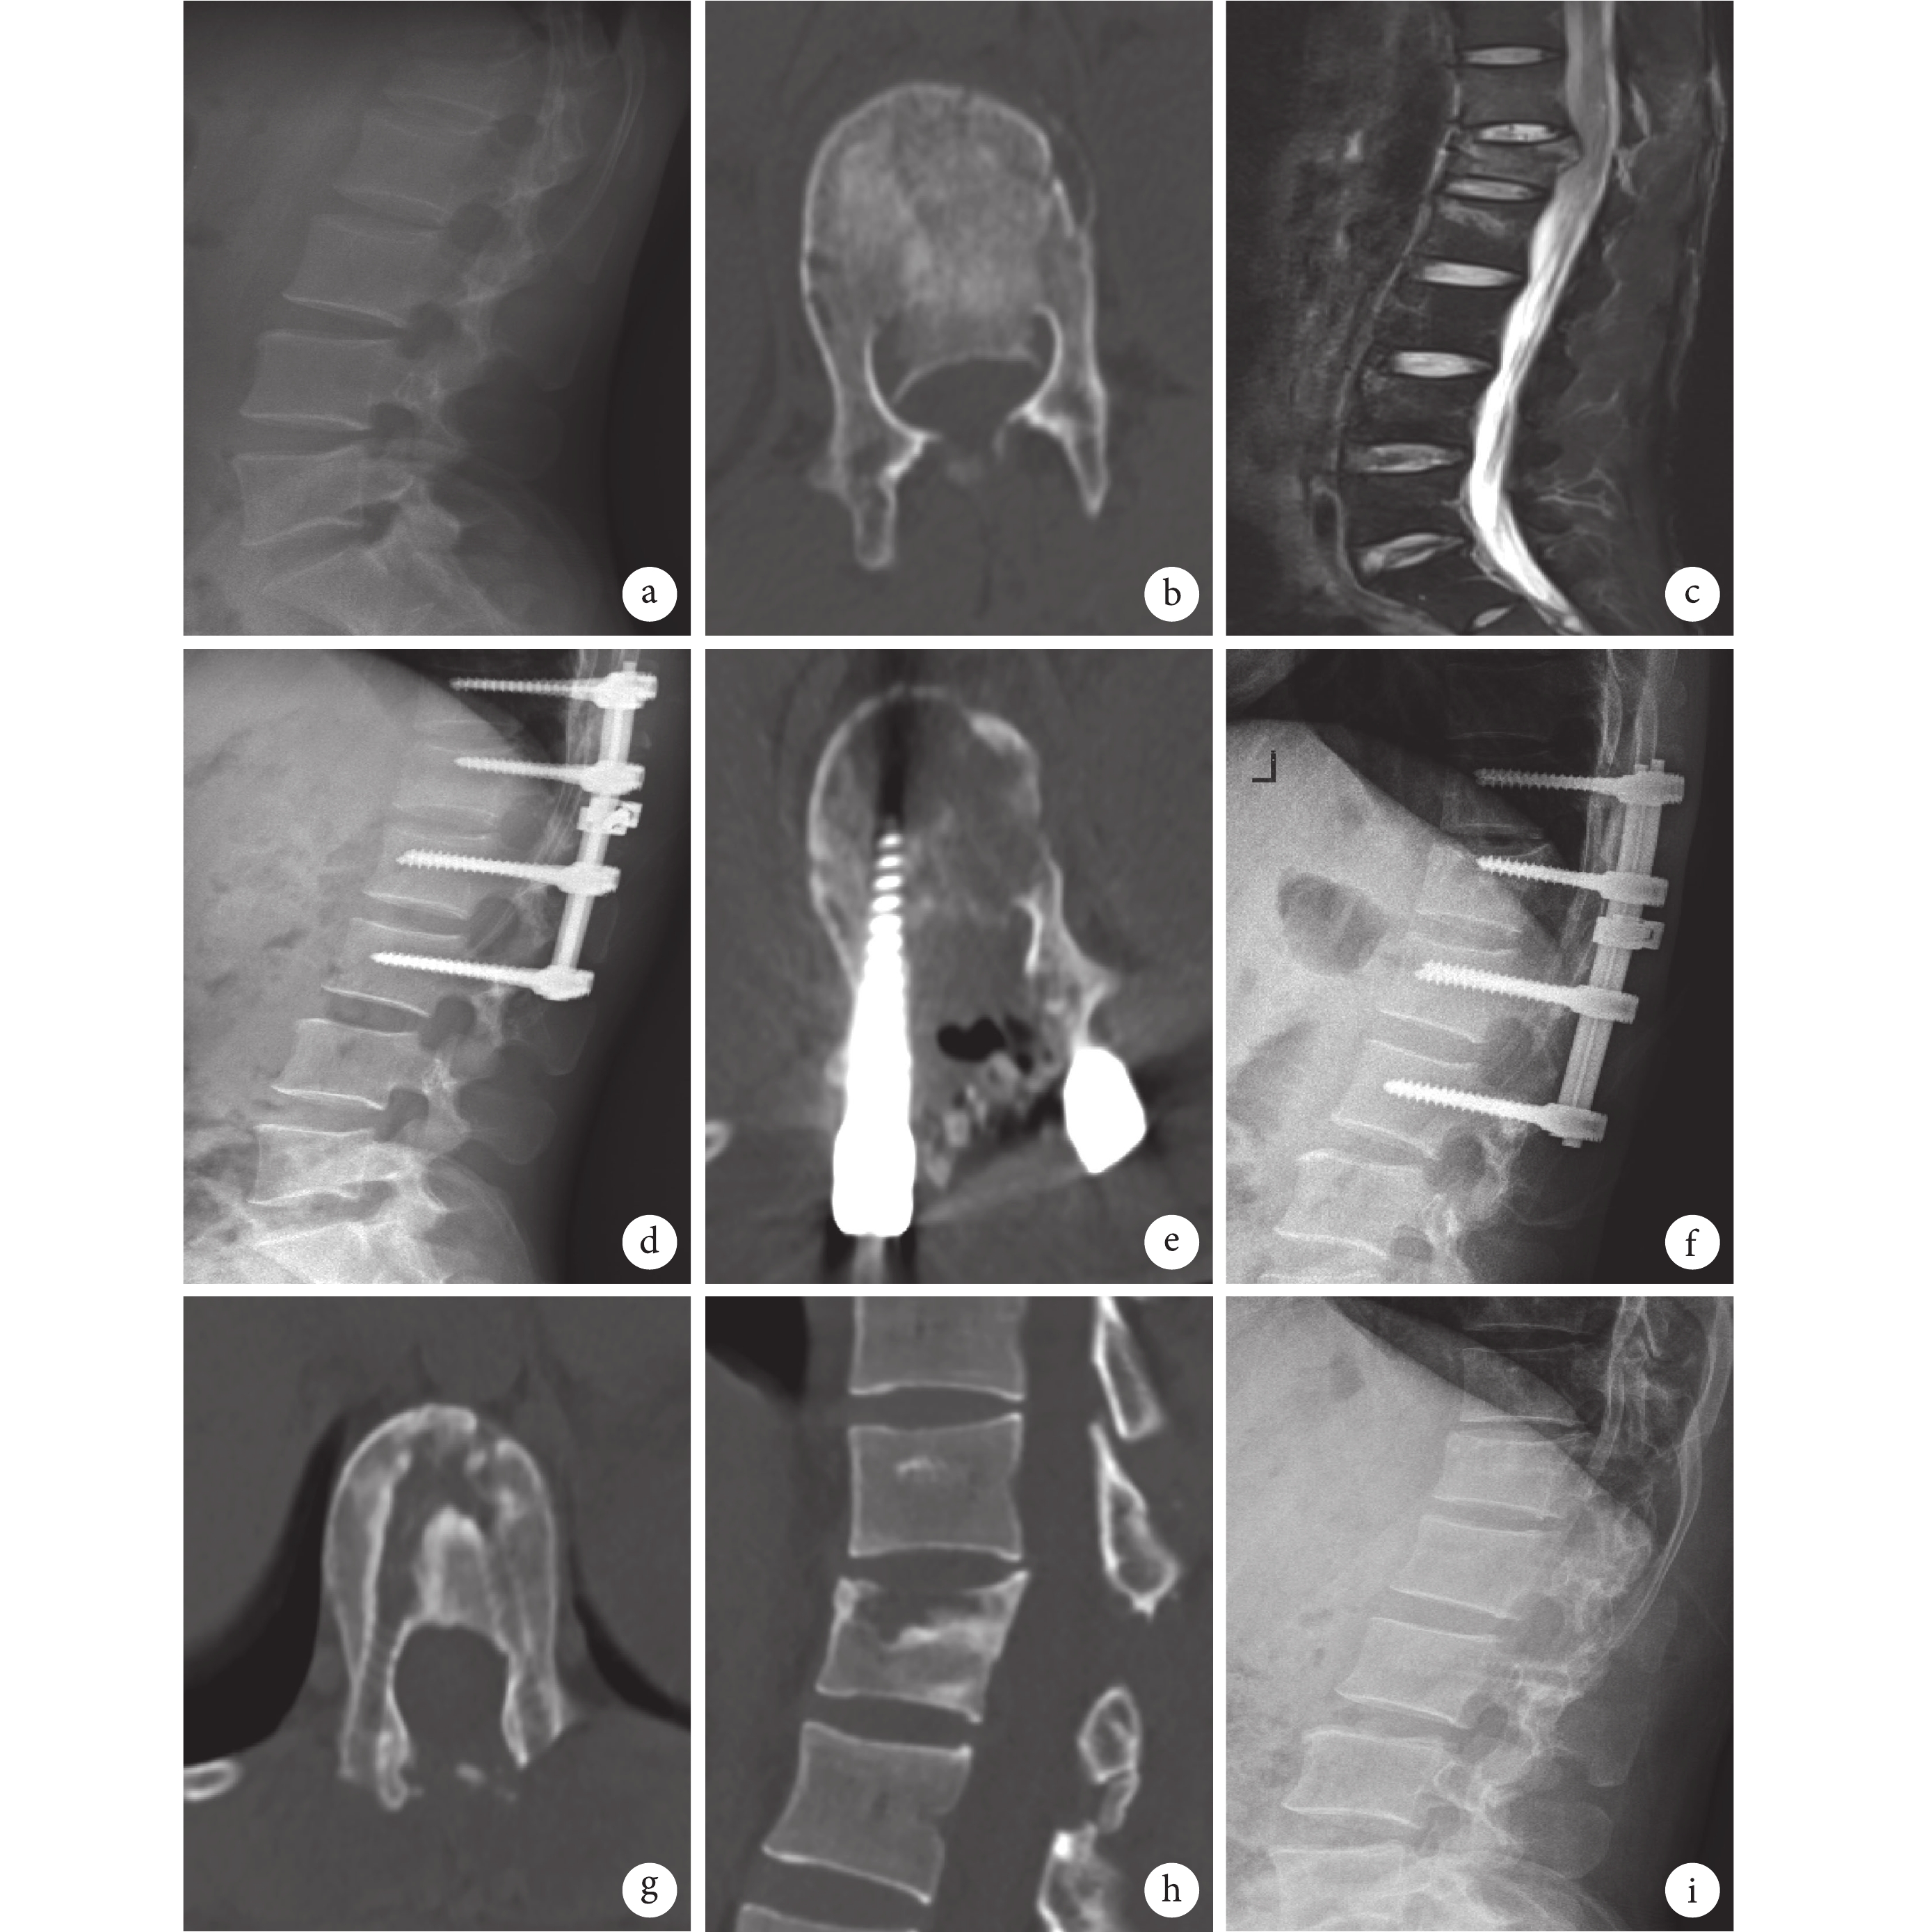

觀察組患者,男,54 歲,因車禍傷致腰背部疼痛活動受限伴右下肢麻木 3 h 入院,影像學資料顯示:胸椎 12 爆裂性骨折,椎體明顯壓縮,椎管占位,Frankel 分級 D 級。患者行 Wiltse 入路椎弓根釘內固定復位+單側椎板有限開窗新型夯實器復位椎管內骨折塊+后外側植骨融合術,術后 3 d隨訪復查 CT 示椎管骨折塊復位、減壓良好,右側椎板有限開窗減壓后關節突咬合關系存在。見圖1。

a. 術前 CT 示胸椎 12 爆裂性骨折,椎體明顯壓縮;b. 術前 MR 示胸椎 12 爆裂性骨折,脊髓明顯受壓;c. 術前 CT 示胸椎 12 爆裂性骨折,椎管嚴重占位;d. 術中使用新型夯實器夯實復位椎體后壁骨折塊 C 型臂透視像;e. 術后 3 d X 線片正位示傷椎高度恢復良好;f. 術后 3 d X 線片側位示傷椎高度恢復良好;g. 術后 3 d 橫斷位 CT 示椎管骨折塊復位、減壓良好,椎體內無空殼;h. 術后 3 d 冠狀位 CT 顯示右側椎板有限開窗減壓后關節突咬合關系存在;i. 術中應用的新型復位夯實器